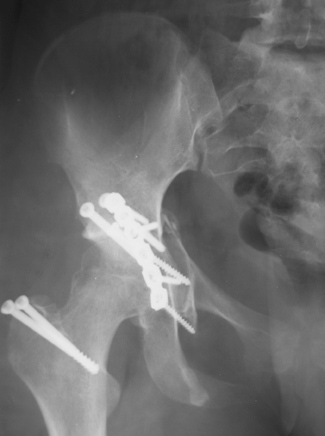

30/11/04 |  30/11/04 |  30/11/04 |  14/12/04 |  14/12/04 |  14/02/05 |  14/02/05 |  21/02/05 | Уважаемые коллеги! Случилось вторичное смещение вертлужной впадины после операции. Посоветуйте, что делать. Пациентка 18 лет. Травма 19.11.04. D.s.: Закрытыый Т-образный высокий перелом правой вертлужной впадины. Закрытый перелом м\мыщелкового возвышения левой б\берцовой кости. 9.12.04 операция - открытая репозиция, остеосинтез переломам вертлужной впадины. 30.12.05 выписаны на амбулаторное лечение с рекомендациями не вставать на правую ногу. 14.02.05 при контрольном осмотре на Р-граммах выявлено вторичное смещение передней колонны. Клинически подвывиха нет, имеется умеренная приводящая контрактура правого тазобедренного сустава, гипотрофия мышц н\конечностей. Госпитализирована в травмотделение. Выполнено КТ. Имеется смещение передней колонны кнутриЮ диастаз 8 мм. Посоветуйте пожалуйста, что предпринять в данной ситуации.